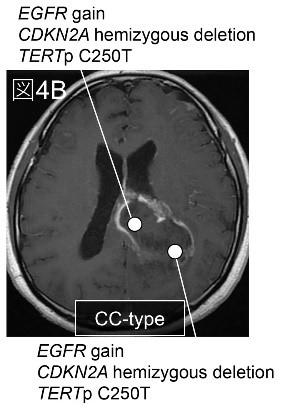

【マルチサンプリング解析】手術時にマルチサンプリングが6例で可能でありました。画像解析で大脳半球タイプであった3例のうち2例で、大脳半球腫瘍に比し脳梁部腫瘍で遺伝子変異の蓄積を認め、分子学的に大脳半球から脳梁方向に進展していることが示唆されました (代表例図4A)。一方で、画像解析で脳梁タイプであった3例全例で、大脳半球と脳梁の変異が同じでマルチサンプリングで進展方向を示唆することはできませんでした (図4B)。